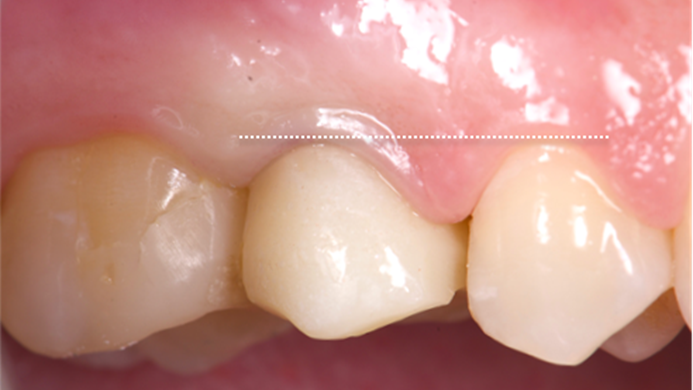

Clinical case: Extraction, immediate implant placement, & provisionalization

- Courtesy of Dr. Iulian Filipov, Romania -

Keywords

AnyRidge, R2GATE, guided surgery, immediate placement, immediate provisionalization, initial stability, Dr. Iulian Filipov, #25, maxillary posterior, immediate loading, Mega ISQ